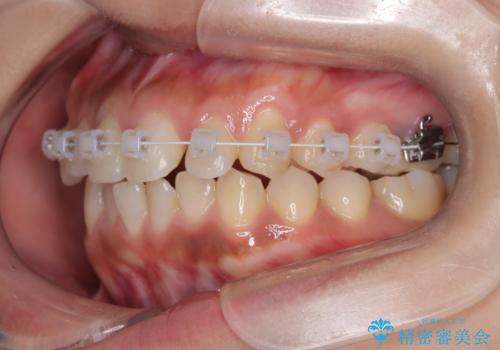

臼歯部の反対咬合を改善|MARPEによる上顎急速拡大+審美ワイヤー矯正

- 患者様は、奥歯(臼歯部)の反対咬合を主訴に来院されました。反対咬合は、噛み合わせのズレや顎の成長に影響を与える可能性があるため、早期の治療が重要です。診断の結果、上顎の幅が不足していることが原因と判明し、MARPE(骨固定式上顎急速拡大装置)を用いて上顎を広げる治療を計画しました。その後、歯列の調整のために審美ワイヤー矯正を行う方針としました。

MARPEを使用して上顎を拡大し、適切な歯列のスペースを確保しました。この拡大によって、反対咬合が改善され、正常な噛み合わせへと誘導できました。その後、目立ちにくいブラケットと白いワイヤーを使用した審美ワイヤー矯正を行い、歯列を整えました。治療が進むにつれ、噛み合わせのバランスが良くなり、見た目も自然な仕上がりに。

患者様からも「しっかり噛めるようになり、見た目も気にならなくなった」と満足の声をいただきました。